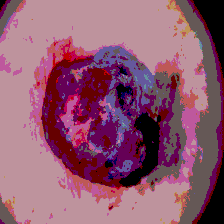

Timely identification and treatment of rapidly progressing skin cancers can significantly contribute to the preservation of patients' health and well-being. Dermoscopy, a dependable and accessible tool, plays a pivotal role in the initial stages of skin cancer detection. Consequently, the effective processing of digital dermoscopy images holds significant importance in elevating the accuracy of skin cancer diagnoses. Multilevel thresholding is a key tool in medical imaging that extracts objects within the image to facilitate its analysis. In this paper, an enhanced version of the Mud Ring Algorithm hybridized with the Whale Optimization Algorithm, named WMRA, is proposed. The proposed approach utilizes bubble-net attack and mud ring strategy to overcome stagnation in local optima and obtain optimal thresholds. The experimental results show that WMRA is powerful against a cluster of recent methods in terms of fitness, Peak Signal to Noise Ratio (PSNR), and Mean Square Error (MSE).